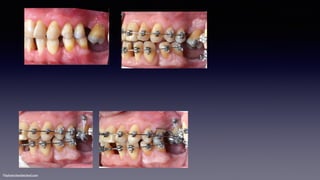

At 15 weeks

•Md: 16x22 cnt

•Mx: ∆EC. .016 sc™